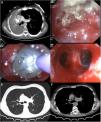

The authors report the case of a 54-year-old male patient submitted to bipulmonary transplant due to chronic obstructive pulmonary disease. According to surgical registries, a continuous running suture on membranous and an interrupted suture on cartilaginous portion of bronchus was made. Surveillance bronchoscopy was performed during the first three months without evidence of airway complications. The patient was immunosuppressed with tacrolimus and mycophenolate. Eight months after transplantation, he developed dyspnea, and functional tests showed marked FEV1 decreased. Chest CT detected complete atelectasis of right lung (Fig. 1A) and bronchoscopy occlusion of right main bronchus by a yellowish hard mass (Fig. 1B). Histological and microbiological examination confirmed Aspergillus infection. The patient underwent rigid bronchoscopy with mechanical desobstruction (Fig. 1C and D) and began therapy with amphotericin B followed by posaconazole. A follow-up CT image, four months after, showed marked improvement with resolution of atelectasis, however, with a stenosis in the emergence of right upper lobar bronchus (Fig. 1E). The patient maintains endoscopic and microbiologic surveillance, according to clinical and functional evolution.

Aspergillus infections are common following lung transplantation, with diverse and complex manifestations.1,2 Anastomotic infections should be a complication to fear despite antifungal prophylaxis. Routine bronchoscopy plays an important role, not only as a means to diagnose but also for therapeutic purposes, namely in early diagnosis of suture complications.